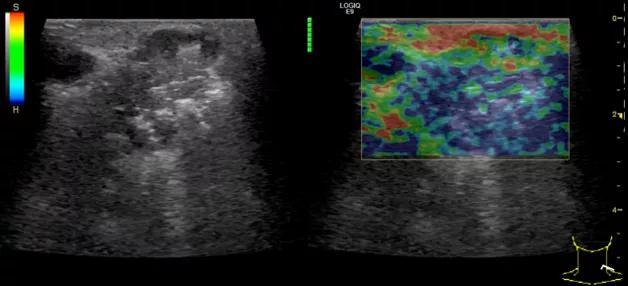

随后,徐栋教授进一步分享了五个临床实战病例,带来了更直观的热消融治疗经验。第一个病例是62岁肺癌患者,术后1年余发现双侧锁骨上淋巴结复发,侵犯神经,存在静脉回流、淋巴回流障碍,肿胀、疼痛非常明显。影像显示患者淋巴结边界不清、形态不规则,存在浸润,血流强化增强。由于患者在系统治疗后进展,且主要目的缓解症状、减瘤。局麻下行热消融术,从后向前逐层消融,热消融之后超声造影即刻评估显示完全充盈缺损,完全覆盖病灶。

(病例1图例)